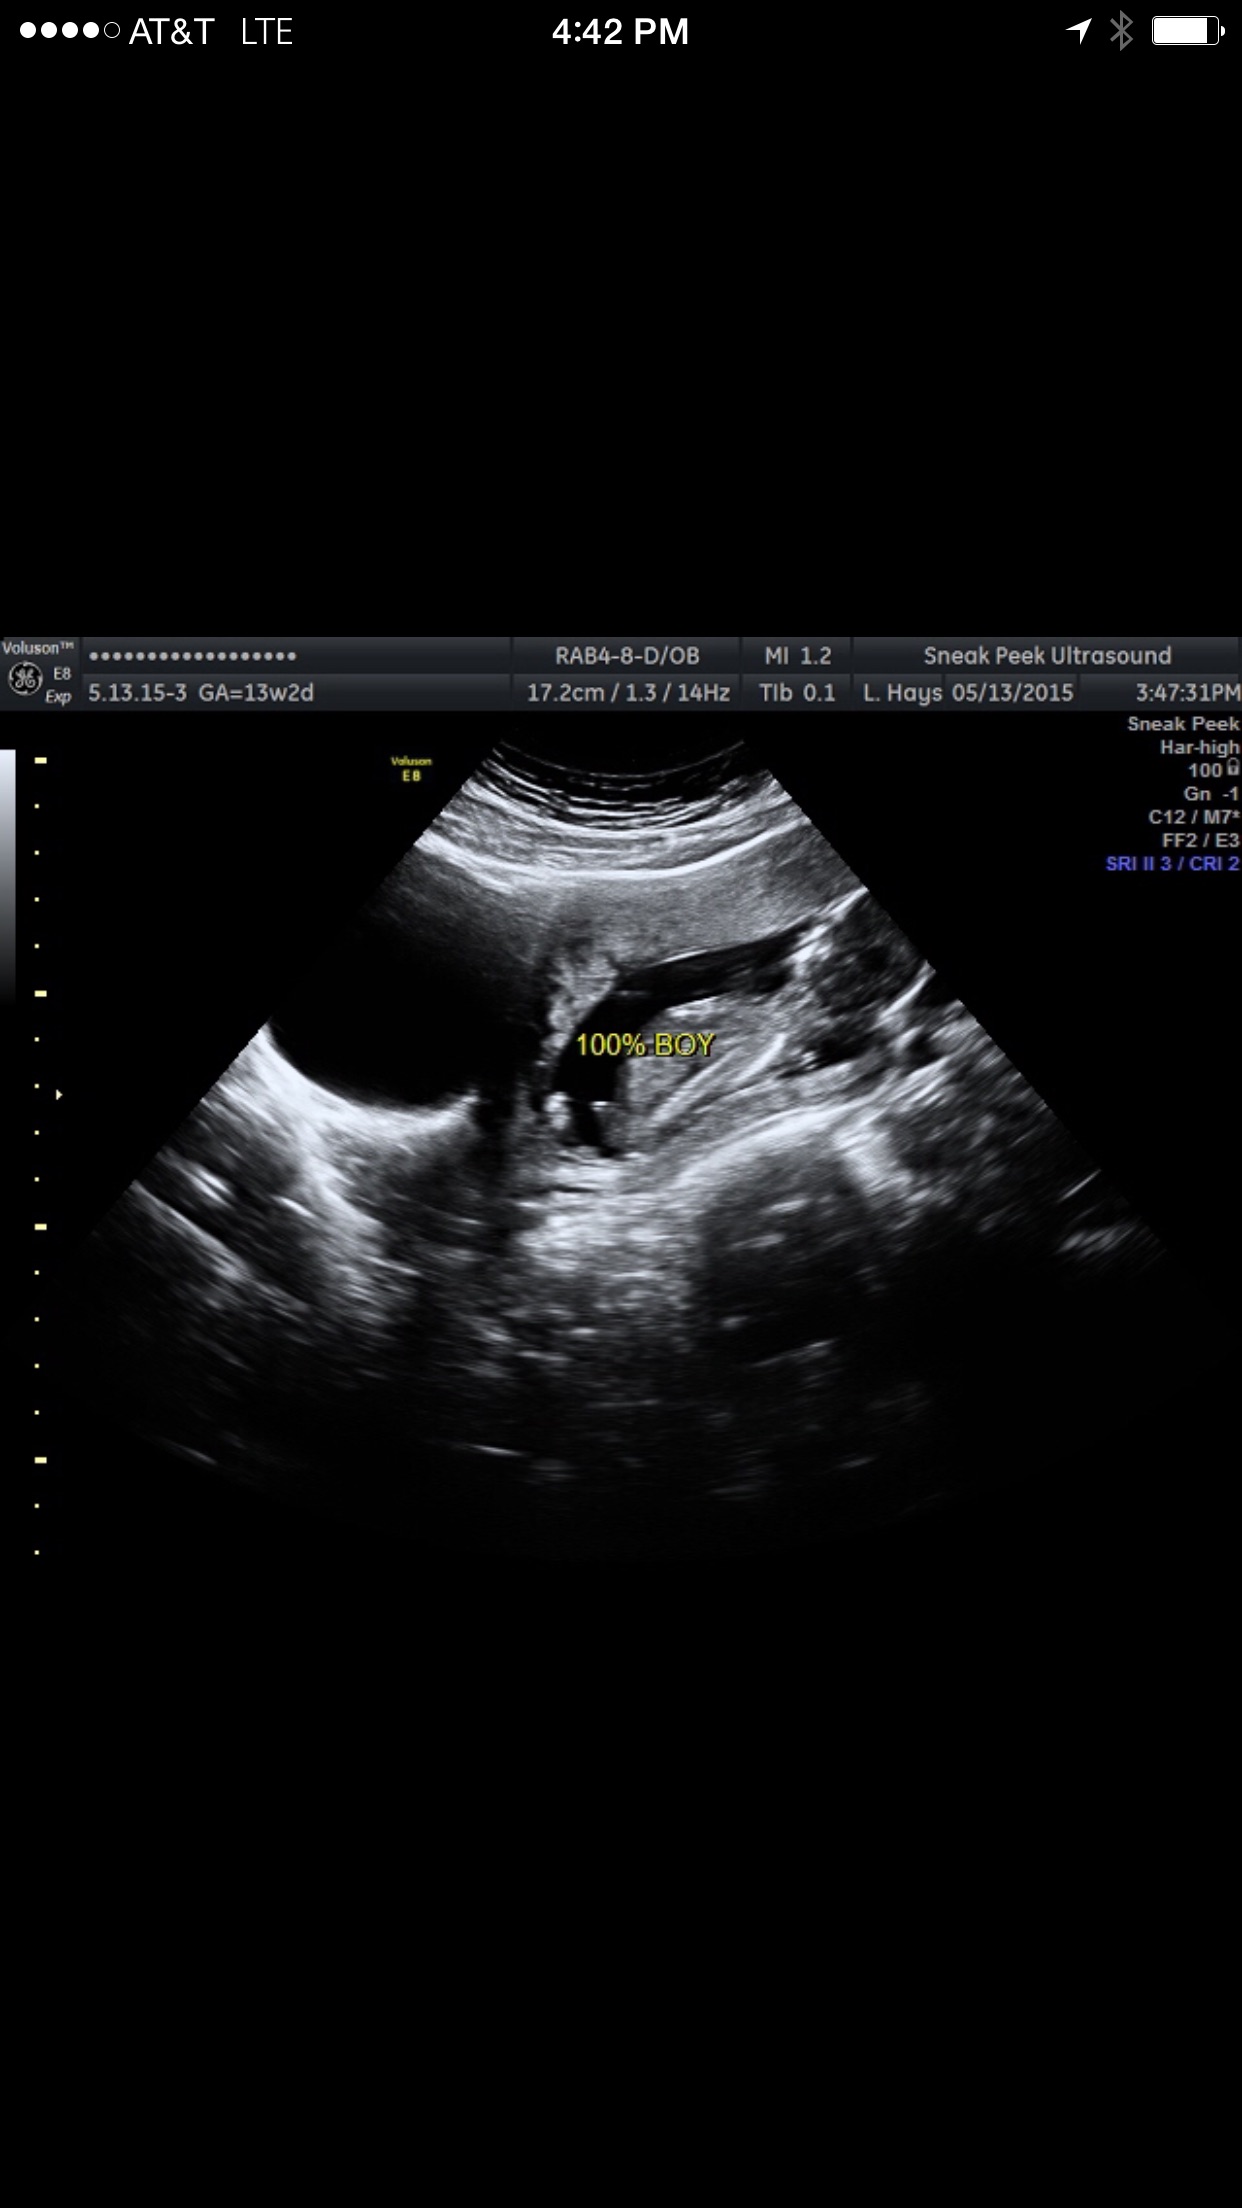

I don't want to guess on anyone's but you can use mine for reference.

My OB came in at a different angle so no guessing was needed, he just scanned my side where babies bottom was and we could clearly see he is a baby boy

Definately a boy to me